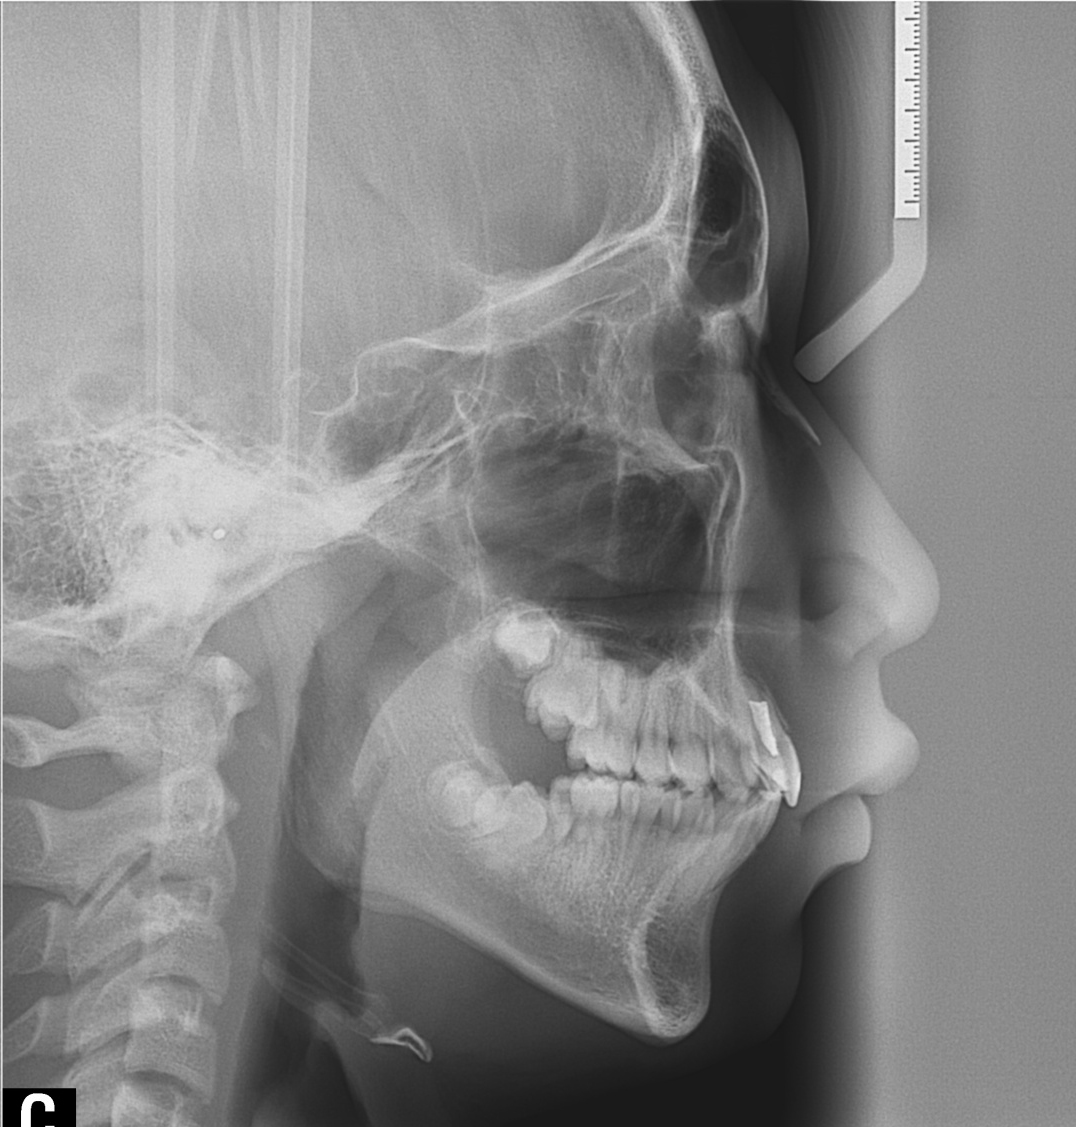

À§ ȯÀÚ´Â À´Ï°¡ ¾Æ·§´Ï¸¦ ³Ê¹« µ¤¾î¿ä(°ú°³±³ÇÕ) ¸¦ ÁÖ¼Ò·Î ³»¿øÇÑ ÃʵîÇлýÀ̾ú½À´Ï´Ù. ÅμºÀå ¾ÇÁ¤ÇüÀåÄ¡ »ç¿ëÈÄ È£ÈíÀÌ °³¼± µÇ¾úÀ¸¸ç Ä¡·áÀü¿¡ ºñÇØ ۰¡ 10cmÁ¤µµ ±Þ¼Ó ¼ºÀåÇÏ¿´½À´Ï´Ù.

°ú°³±³ÇÕ°ú ¹«ÅÎ,ÅΰüÀýÀ» ÁÖ¼Ò·Î ³»¿øÇÏ¿© ÅμºÀå ¾ÇÁ¤ÇüÀåÄ¡¸¦ ÀÌ¿ëÇÏ¿© Ä¡·áÁßÀΠȯÀÚ·Î Ä¡·á½ÃÀÛ½ÃÁ¡ ±âÁØÀ¸·Î ÇöÀç ۰¡ ¾à 8cmÁ¤µµ ¼ºÀåÇÏ¿´½À´Ï´Ù. (Âü°í·Î 2³âÂ÷ ¿©µ¿»ý°ú ۰¡ 7-9cmŰ Â÷À̳²)